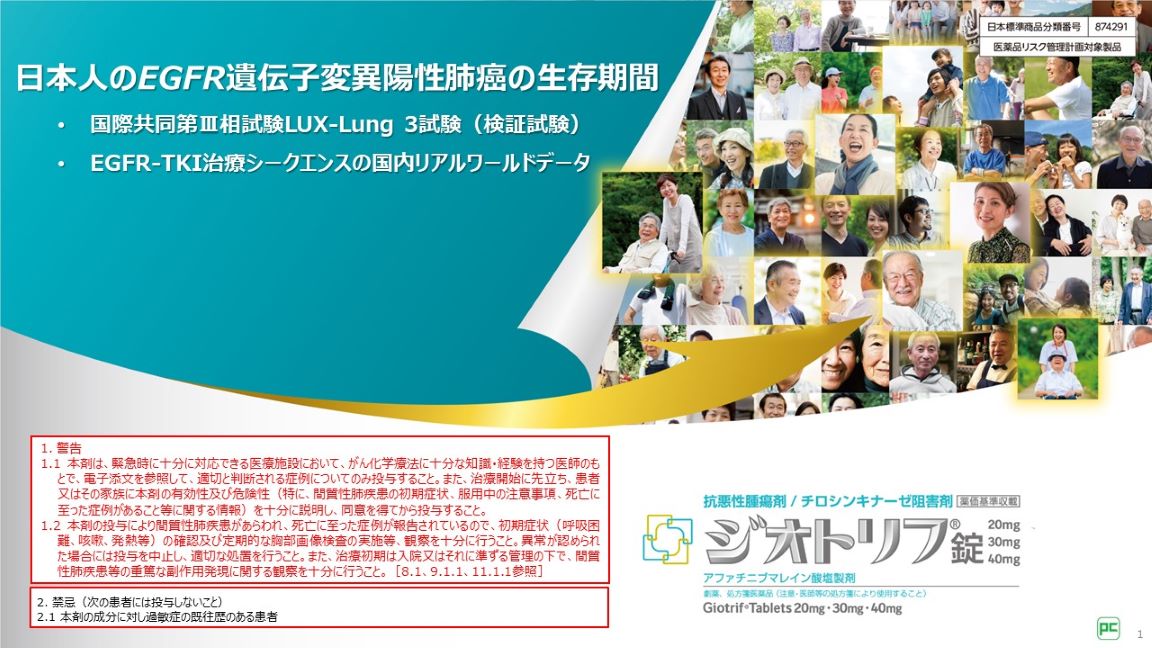

Amazon.co.jp: エッセンシャル遺伝学・ゲノム科学(原著第7版。エッセンシャル遺伝学・ゲノム科学(原著第7版) | Daniel L。Amazon.co.jp: エッセンシャル遺伝学・ゲノム科学(原著第7版。専用 水出しアイスティー トロピカルフルーツ 水出し アイスティー リプトン。幹細胞を制御する糖鎖。エッセンシャル遺伝学・ゲノム科学(原著第7版) | Daniel L。エッセンシャル遺伝学・ゲノム科学(原著第7版) - 株式会社。遺伝子検査 | SB TEMPUS。ヒトヘルペスウイルス7型遺伝子検出試薬|タカラバイオ株式会社。HUMAN(人) | Okinawa Institute of Science and Technology OIST。。【内容紹介】本書は遺伝学とゲノム科学の基本的な概念を網羅した教科書です。第7版では最新の研究成果が反映され、より深い理解を促します。エッセンシャル遺伝学・ゲノム科学(原著第7版) | Daniel L。【特徴】豊富な図表と具体例を用いて、難解な内容をわかりやすく解説しています。専門家だけでなく、学生にも適した内容です。東北大学 大学院農学研究科・農学部。【用途】遺伝学やゲノム科学を学ぶ学生、研究者に最適な一冊です。基礎から応用まで幅広くカバーしています。日本人のEGFR遺伝子変異陽性非小細胞肺癌の生存期間 | べー。- 書名: エッセンシャル 遺伝学・ゲノム科学- 版: 第7版- 著者: ダニエル・L・ソートル- 翻訳者: 中村千春・岡田真希子- 出版社: 化学同人ご覧いただきありがとうございます。